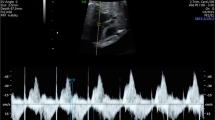

All ultrasound examinations were performed with a commercially available echocardiographic machine (Vivid 7 Dimension System; Vingmed-General Electric, Horten, Norway). The examinations were performed using a 4-MHz convex probe and a large-scale segmental analysis. Cardiac structural assessment was performed using segmental sequential analysis. The IVS septum, left-ventricular (LV), and right-ventricular (RV) end-diastolic diameters were measured using M-mode echocardiography. IVS thickness was measured at end-diastole in M-mode echocardiography. Interventricular hypertrophy was defined as an IVS septum thickness >2 SDs according to gestational age [6]. In the four-chamber view of the fetal heart, the cursor was placed perpendicular to the IVS, just below the tips of the atrioventricular valves. The end-diastolic dimension (EDD) and the end-systolic dimension (ESD) of the LV and RV were measured by M-mode. LV and the RV shortening fractions were calculated as (EDD − ESD)/EDD. Diameters of the aortic and pulmonary annulus were measured three times in frozen real-time images during systole using the leading edge-to-leading-edge method, and their mean value was used for further analysis.

Mitral and tricuspid inflow velocities were measured in apical four-chamber view using pulsed-wave Doppler at the leaflet tips of the mitral and tricuspid valves. Peak systolic velocity waveforms from the ascending aorta were obtained from the five-chamber view. Peak systolic velocity waveforms from the pulmonary artery were obtained from the short-axis view. In both vessels, the Doppler sample volume was placed immediately distal to the semilunar valves.

The fetal cardiac tissue Doppler imaging (TDI) was performed in four-chamber view. The imaging was performed when fetal body movements paused after the mother was asked to hold her breath. Particular attention was also paid to keep the angle of insonation <20° while the tissue Doppler and pulsed-wave velocities were obtained. No angle correction of the Doppler signal was applied. In the TDI and the pulsed-wave Doppler measurements, the average of three successive pulses was taken. Right and left myocardial velocities were obtained from the apical four-chamber view. The sample volume was placed at three basal myocardial positions: the LV posterior wall, the IVS, and the RV free wall. The sample volume width measured approximately 1 mm. The Nyquist limit was adjusted to 15–20 cm/s. The mean peak values of three early diastolic waves (E a) and of three late diastolic or atrial filling waves (A a) were registered, and the mean ratio of the peak velocities of the E a and A a waves in each position (E a/A a ratio) was determined. The mean peak values of three systolic waves (S a) were registered. LV E/E a ratios were also calculated.

In the measurement of the LV myocardial performance index (MPI), the E/A waveform was always kept positive, whereas the angle of insonation was always kept at <20° [10]. The four-chamber view was taken, and the apical view of the heart was obtained. To measure the MPI, the Doppler cursor was placed on the lateral wall of the ascending aorta just below the aortic valve and next to the mitral valve. The waves reflecting systole and diastole were obtained in combination. At the beginning and the end of the aortic valve wave forms, a clear echo was formed in the Doppler tracing corresponding to the opening and closing of the two valves. Measurements at three time intervals were performed using pulsed-wave Doppler. These intervals were the isovolumetric contraction time (IVCT [time interval from the closure of the mitral valve to the opening of the aortic valve]), the ejection time (ET [time interval between the opening and the closure of the aortic valve]), and the isovolumetric relaxation time (IVRT [time interval from the closure of the aortic valve to the opening of the mitral valve]). The MPI was calculated by the following formula: (IVCT + IVRT)/ET. All studies were recorded on videotape and as hard copies. Measurements were performed by a single operator who was blinded to hypothesis and patients’ clinic status.